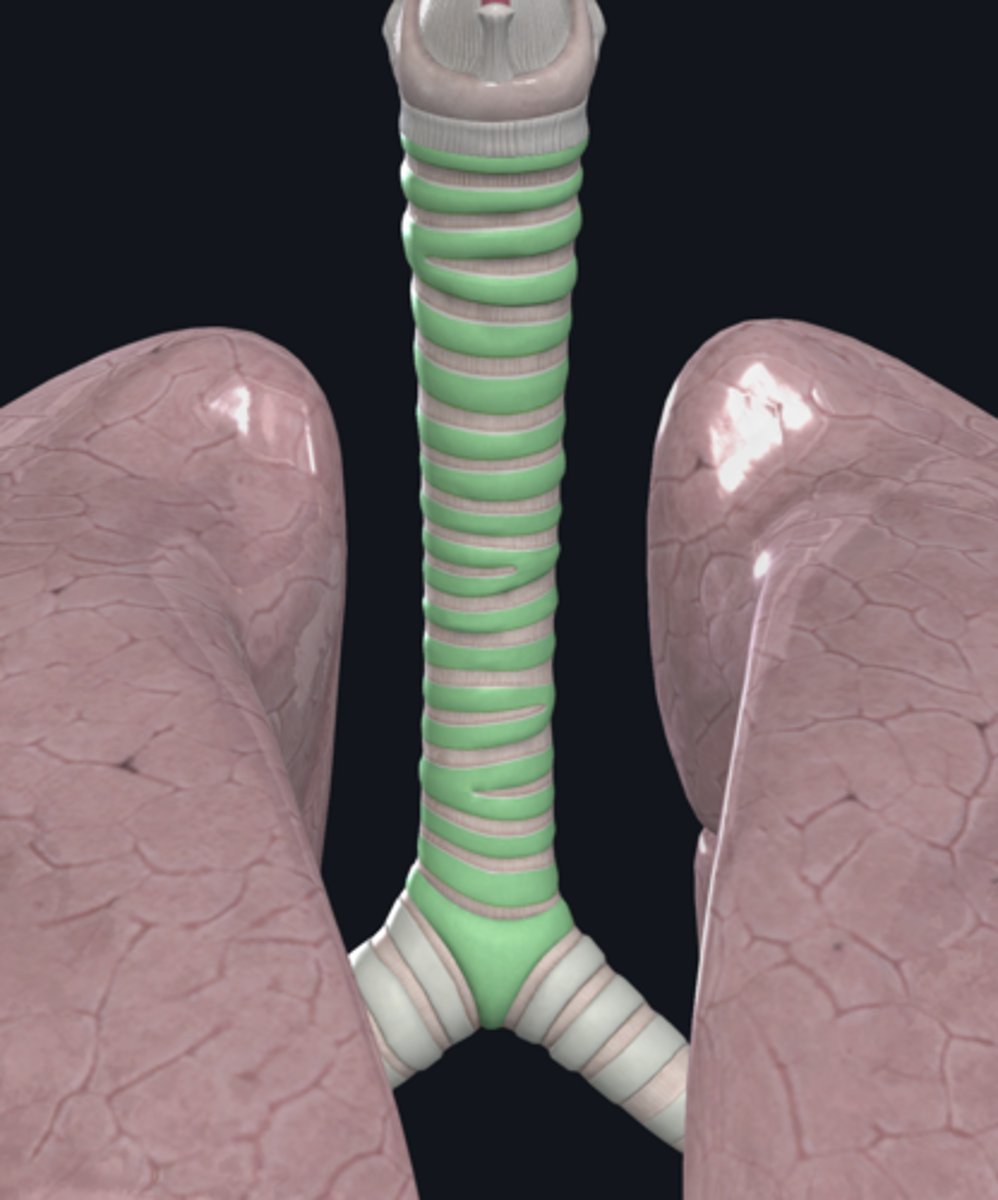

trachea

tracheal cartilage

trachea

tracheal cartilages

annular ligament

right main bronchus

left main bronchus

lobar bronchi

terminal bronchi